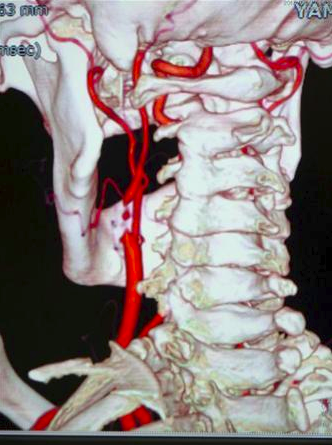

ナタリーさんの首にある大動脈が切れていのです!

幸い、応急手術をして大動脈は治療できましたが、脳にあった血栓は溶かすことができませんでした。でも、血栓は時間が経てば自然に消えるだろうといこうことでした。